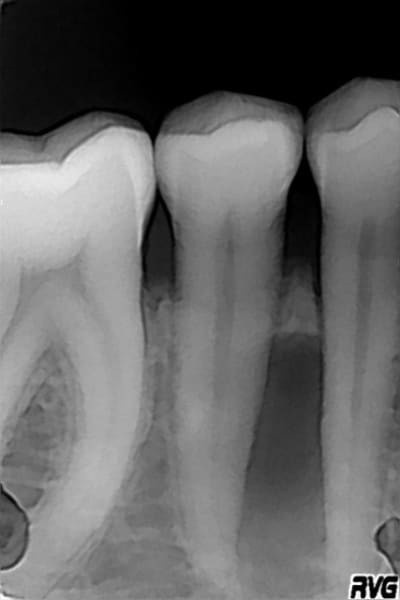

Bonjour, que penser de ce cas?

Deux radios à 1 an d'intervalle.

Peu de symptômes à part une petite douleur à la pression masticatoire, et sensibilité légère à la percussion tant axiale que latérale.

la 44 ne répond pas au test au froid, 45 est vivante.

je pense à une nécrose spontanée de 44 et la présence d'un canal latéral perpendiculaire dans le tiers apical, d'ou ce granulome...

En dehors des trucs classiques associés à un problème paro, endo ou endo-paro, si les complément radiomontrent rien d'autre (ce que je pense être le cas ici) il faut évoquer ici un rare kyste latéral périodontal vis à vis de la topographie

Résultats de la 3D : la lacune semble être en rapport avec l'apex de 45, bien que ce ne soit pas certain. Decision a été prise de vérifier à la fraise sans anesthesie la vitalité réelle de 44 et 45, et de traiter le canal de celle qui ne réagit pas. Peut être les deux... A suivre....

La 44 a été traitée. Pas de parenchyme jusqu'au 1/3 apical, et là une sensibilité nécessitant une anesthesie. Traitement complet du canal. Obturation à la gutta. Controle radio montrant une obturation correcte, mais pas de canal secondaire ou latéral.

D'accord avec Canin pour un kyste odontogène parodontal latéral, évolutif au détriment de l'os environnant. Ca y ressemble. Très rare mais quand il est présent, ça peut se présenter entre les prémolaires mandibulaires.

L'alvéolyse horizontale est-elle uniquement localisée au niveau de ces deux dents ou est-elle généralisée à l'ensemble de la mandibule ? As-tu une perte d'attache, un saignement au sondage ? Une tuméfaction gingivale en regard ?

Alveolyse localisée uniquement entre les deux dents. Pas de perte d'attache, pas de saignement, ni de tuméaction gingivale . Juste une petite sensation de pression entre les deux dents.

Enucléation dans quelques jours.

Pour info, la lésion a été curetée il y a quelques jours, lambeau, curetage soigneux, lavage de la cavité ( le kyste est venu en entier avec la paroi ), comblement au Bio-Os, pose d'une membrane, et sutures .